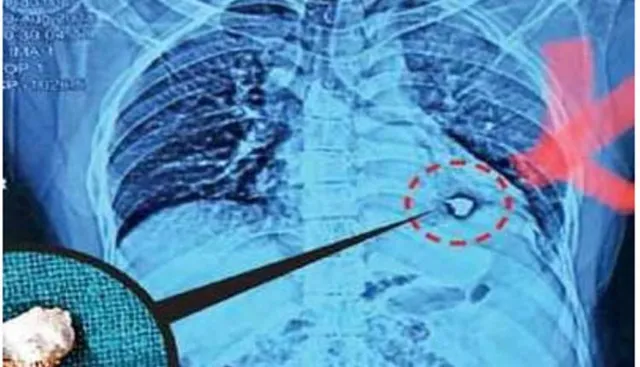

ଯୁବକଙ୍କ ହୃଦୟରୁ ବାହାରିଲା ୪ ସେଣ୍ଟିମିଟର ଲୁହାର କଣ୍ଟା ! ବିପଦ ଥିବା ଜାଣି ମଧ୍ୟ ସଫଳ ଅସ୍ତ୍ରୋପଚାର କଲେ ଡାକ୍ତର

କନକ ବ୍ୟୁରୋ : ସତୀଶ କୁମାରଙ୍କ ପୁର୍ନଜନ୍ମ ହୋଇଛି ବୋଲି ତାଙ୍କ ସାଙ୍ଗମାନେ କହୁଛନ୍ତି। ଉତ୍ତରପ୍ରଦେଶ ସିକନ୍ଦରାବାଦରେ ଏକ ଷ୍ଟିଲ୍ ଫ୍ୟାକଟ୍ରିରେ କାମ କରୁଥିବା ୩୫ବର୍ଷୀୟ ସତୀଶଙ୍କ ହୃଦୟରେ ଏକ ଲୁହାର କଣ୍ଟା ପଶି ଯାଇଥିଲା । ତାଙ୍କ ଜୀବନ ପ୍ରତି ଥିଲା ବିପଦ, ଏହା ସତ୍ତ୍ୱେ ବି ଡାକ୍ତର ସଫଳତା ସହ ଅସ୍ତ୍ରୋପଚାର କରି ସତୀଶଙ୍କୁ ନୂଆ ଜୀବନ ଦେଇଥିଲେ। ସବୁଦିନ ଭଳି ଅଗଷ୍ଟ ୯ ତାରିଖରେ ବି ସତୀଶ ଫ୍ୟାକଟ୍ରିରେ ଆଇରନ୍ ଡ୍ରିଲିଂ କାମ କରୁଥିଲେ। ଏହି ସମୟରେ ହଠାତ୍ ଏକ ଲୁହା ଖଣ୍ଡ ଛିଟିକି ପଡି ତାଙ୍କ ଛାତିରେ ଗୁଳି ଭଳି ପଶି ଯାଇଥିଲା। ଏହି ଲୁହାର ଖଣ୍ଡ ପାଖାପାଖି ୪ ସେଣ୍ଟିମିଟର ଲମ୍ବା ଥିଲା ବୋଲି ଡାକ୍ତରଙ୍କ ସୂତ୍ରରୁ ପ୍ରକାଶ। କ’ଣ ହେଲା କିଛି ବୁଝିବା ପୂର୍ବରୁ ସତୀଶ ଚଟଣାରରେ ଟଳି ପଡିଥିଲେ ଓ ତାଙ୍କ ଛାତିରୁ ରକ୍ତସ୍ରାବ ହେବାରେ ଲାଗିଥିଲା।

publive-imageସଙ୍ଗେସଙ୍ଗେ ସତୀଶକୁ ତା’ର ସାଙ୍ଗମାନେ ସ୍ଥାନୀୟ ହସ୍ପିଟାଲକୁ ଚିକିତ୍ସା ପାଇଁ ନେଇଯାଇଥିଲା। ହୃଦୟ ଯାଏ ଏହି ଲୁହାଖଣ୍ଡ ପହଞ୍ଚିଥିଲେ ହେଁ ସୌଭାଗ୍ୟବଶତଃ ସେ ବର୍ତ୍ତି ଯାଇଥିବା ଡାକ୍ତର ସୂଚନା ଦେଇଥିଲେ। ଯଦି ଠିକ୍ ସମୟରେ ତାଙ୍କ ସର୍ଜରି ହୋଇ ନଥାଆନ୍ତା ତେବେ ସତୀଶଙ୍କ ମୃତ୍ୟୁ ବି ହୋଇଯାଇଥାଆନ୍ତ! ସତୀଶ ସହିତ କାମ କରୁଥିବା ତିନିଜଣ ଲୋକଙ୍କ କହିବାନୁସାରେ, ସିକନ୍ଦରବାଦର ତିନିଟି ହସ୍ପିଟାଲ ସତୀଶଙ୍କ ସର୍ଜରୀ କରି ପାରିବେ ନାହିଁ ବୋଲି ମନା କରି ଦେଇଥିଲେ। ଶେଷର ନୋଏଡାର ଏକ ଫୋର୍ଟିସ୍ ହସ୍ପିଟାଲରେ ଡାକ୍ତର ସୁରକ୍ଷିତ ଭାବେ ସର୍ଜରୀ ଅସ୍ତ୍ରୋପଚାର କରାଯାଇଥିଲା। ଏହି ଘଟଣାକୁ ଏକ ମାସ ବିତି ସାରିଛି। ଏବେ ସତୀଶ ସୁସ୍ଥ ଅଛନ୍ତି।